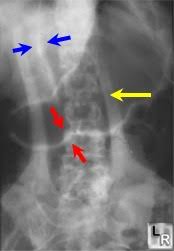

Rigler Sign

See the outline of the small and large bowel outlines - outlined by intraperitonial gas

Free air - Best seen in the right upper quadrant